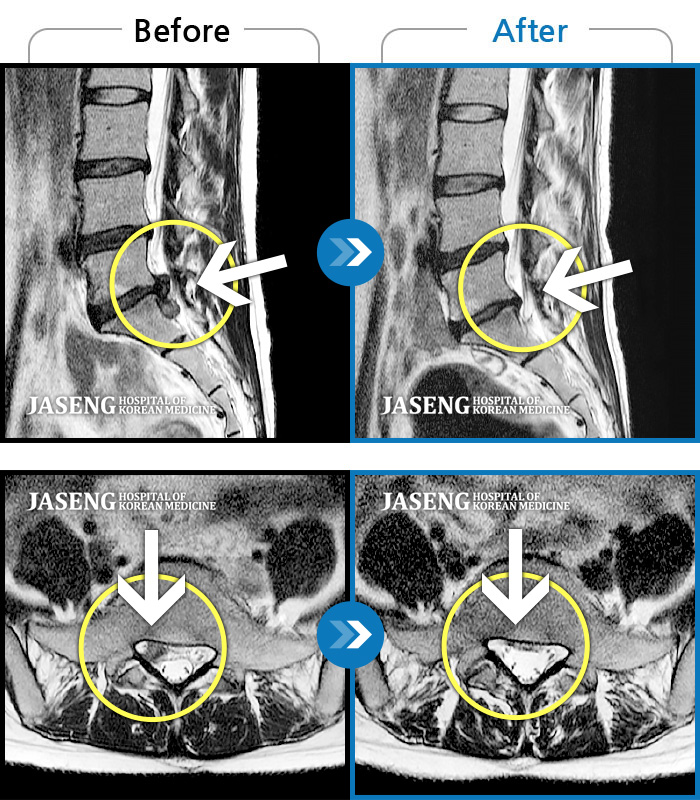

Before

After

허리 통증 및 우측 골반 저림이 심하여 일상생활이 불편한 상태였습니다.

2023.10.12 ~ 2025.11.21